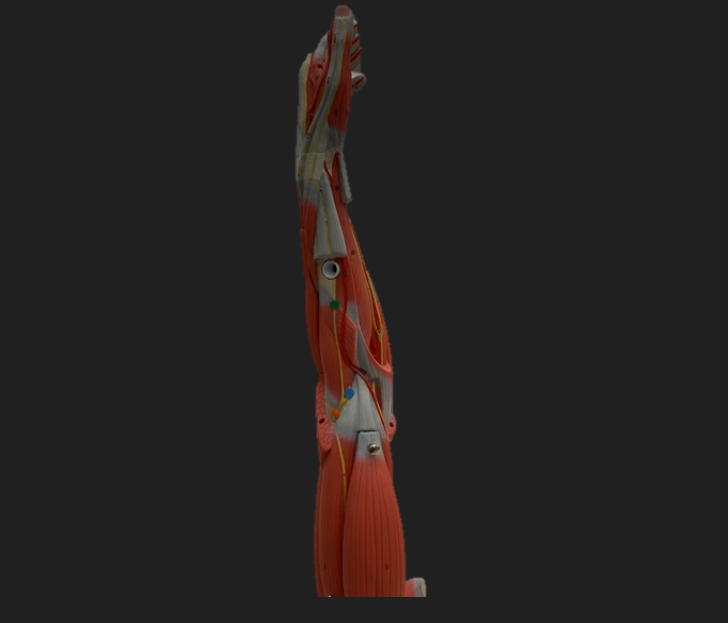

thoracodorsal n.

orange dot

axillary n.

pink dot

musculocutaneous n.

blue dot

median n.

green dot

ulnar n.

orange dot

radial n.

blue dot

deep branch of radial n.

green dot

superficial branch of radial n.